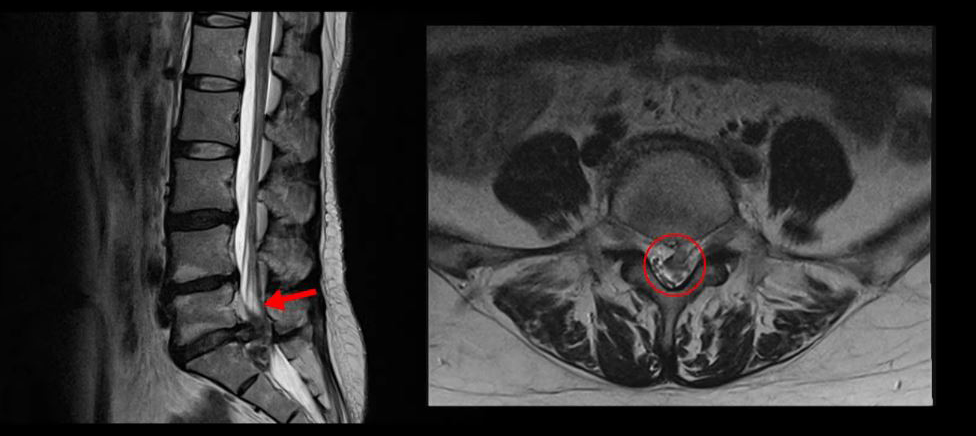

<5-1번 디스크 파열>

이 환자분의 허리 MRI를 보면 5번, 1번 디스크가 매우 심하게 터져 있는 것이 보입니다. 굉장히 심한 허리디스크터짐으로 인해 신경이 있어야 할 곳을 밀려나온 디스크 수핵이 거의 다 차지하고 있는 것을 볼 수 있습니다.

축상면으로 보면 수핵이 위로도 밀려 올라가서 신경 공간을 까맣게 차지하고 있는 것이 보입니다.

아래로도 저 밑에까지 흘러내려가 신경 공간을 많이 차지하고 있어서 신경의 형태가 제대로 보이지가 않습니다.

MRI로 이 정도의 심한 파열이 보이면 다리에 마비나 대소변 장애까지도 있지 않을까 의심될 수 있는 상황인데요. 그래서 환자분이 MRI를 찍은 정형외과에서도 대소변 장애는 없는지 확인하였고, 파열이 심하니까 무조건 바로 수술을 해야 한다고 얘기했다고 합니다. 그런데 다행히도 이 환자분은 다리에 감각 마비와 보행 시 힘 빠짐 증상은 있으나, 대소변 장애는 없었습니다.